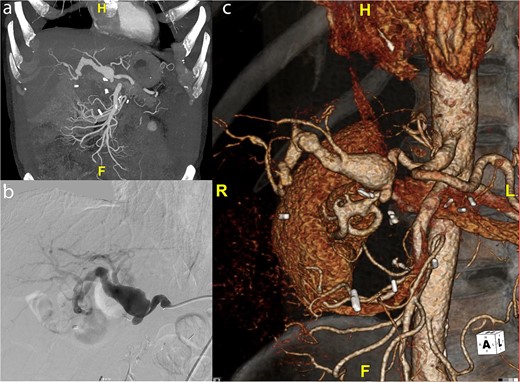

A 59-year-old gentleman was originally referred to vascular surgery in 2011 with a 2.5-cm common hepatic artery aneurysm and was managed conservatively. He had undergone a pancreaticoduodenectomy in 2006 for a presumed pancreatic cancer but was ultimately found to have a benign cyst. The aneurysm was monitored with regular CT scans and grew to 4.2 cm in diameter over the next 9 years and the patient remained asymptomatic. The aneurysm extended from just beyond the origin of the hepatic artery to the first division of the right hepatic artery terminating just before the intraparenchymal portion of the right hepatic artery (Fig. 1a). A catheter-based angiogram was done confirming the extent of the aneurysm and documenting the absence of collateral flow from the superior mesenteric artery (SMA) due to loss of the gastroduodenal artery and other smaller collaterals during the previous Whipple’s procedure (Fig. 1b), which was also evident on 3D reconstruction (Fig. 1c). An endovascular repair was not favored due to the risks of hepatic and biliary ischemia with coiling given the lack of SMA-based collaterals and the inability to place a covered stent. An open repair using a saphenous vein graft was performed.

(a) Preoperative CT scan of hepatic artery aneurysm postremote pancreaticoduodenectomy. (b) Catheter-based angiogram of hepatic aneurysm. (c) 3-D reconstruction of hepatic artery aneurysm.